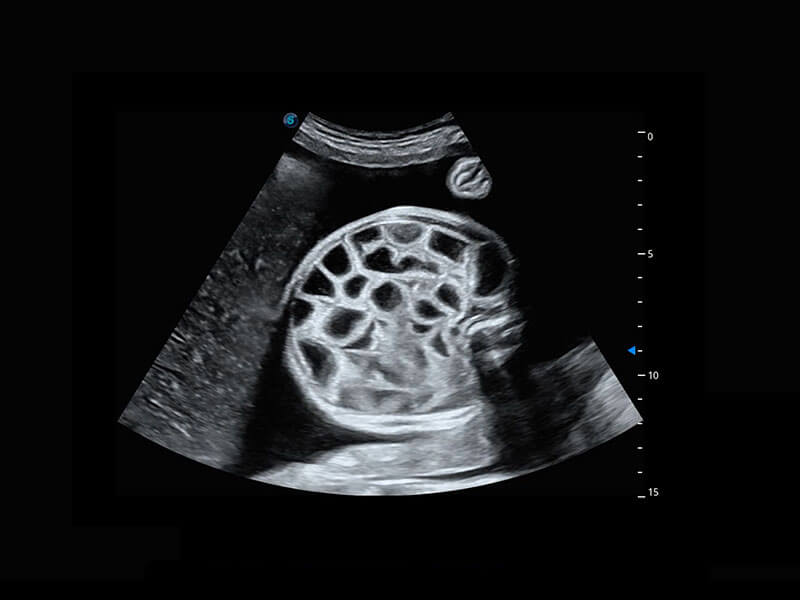

P60優(yōu)異的圖像質(zhì)量搭載專科探頭,在婦科基礎(chǔ)疾病的診斷、卵泡生長(zhǎng)的監(jiān)測(cè)、輸卵管通暢情況的判別等方面為您提供生殖應(yīng)用方案。

腔內(nèi)婦科-卵巢